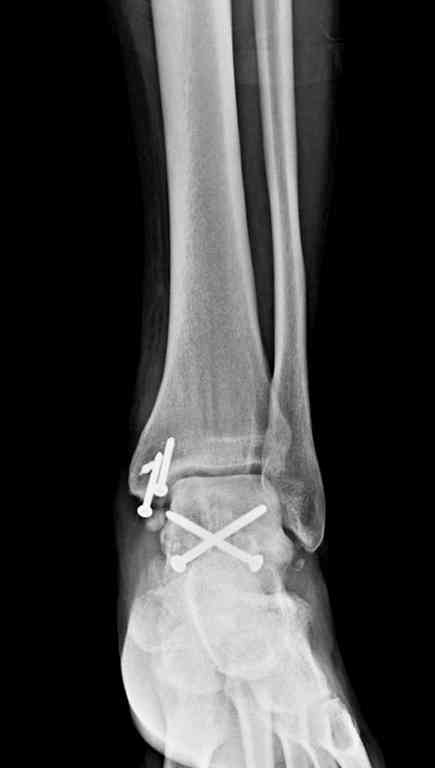

Переломовывих тарана с повреждением медиальной стороны. Через 4 часа после поступления проведена репозиция и фиксация тарана после Irrigation&Debridment. Частичное несращение медиальной лодыжки не беспокоит, вернулся к активному образу жизни. Полная нагрузка разрешена через 11 недель. Финальные снимки через 11 месяцев.

Из-за многооскольчатости дистальной части малоберцовой, где невозможно было провести фиксацию шурупами, перелом зафиксирован подпирающей пластиной, которая должна служить дополнением отсутствующей дистальной части малоберцовой (lateral cortex substitute).

Для стабильности два шурупа на синдесмоз.